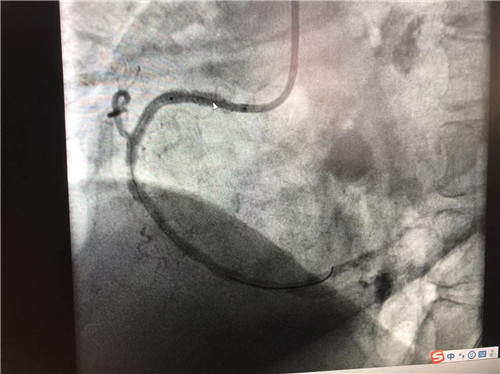

時(shí)間就是心肌,時(shí)間就是生命。導(dǎo)管室內(nèi),心血管內(nèi)科副主任徐先進(jìn)、主任助理農(nóng)彥林已然待命,病人一到,團(tuán)隊(duì)立即為其行深靜脈穿刺泵入血管活性藥物等,情況緩解后,行多體位冠狀動(dòng)脈造影,確認(rèn)RCA(右冠狀動(dòng)脈)近端完全閉塞。經(jīng)家屬同意,在汪念東院長(zhǎng)的指導(dǎo)下,徐先進(jìn)、農(nóng)彥林、張星為患者行經(jīng)皮冠狀動(dòng)脈球囊擴(kuò)張成形術(shù)+經(jīng)外周靜脈穿刺中心靜脈置管術(shù)。術(shù)中,張奶奶再次出現(xiàn)室顫,心血管內(nèi)科團(tuán)隊(duì)臨危不亂,立即予以300焦電除顫搶救,患者竇性心律恢復(fù)。隨后,球囊擴(kuò)張為其置入心臟支架,復(fù)查造影顯示血管恢復(fù)暢通,無明顯夾層,殘余狹窄不到10%。術(shù)后,張奶奶血壓偏低,轉(zhuǎn)入ICU無創(chuàng)呼吸監(jiān)護(hù),2天后轉(zhuǎn)回心血管內(nèi)科護(hù)理。

術(shù)后